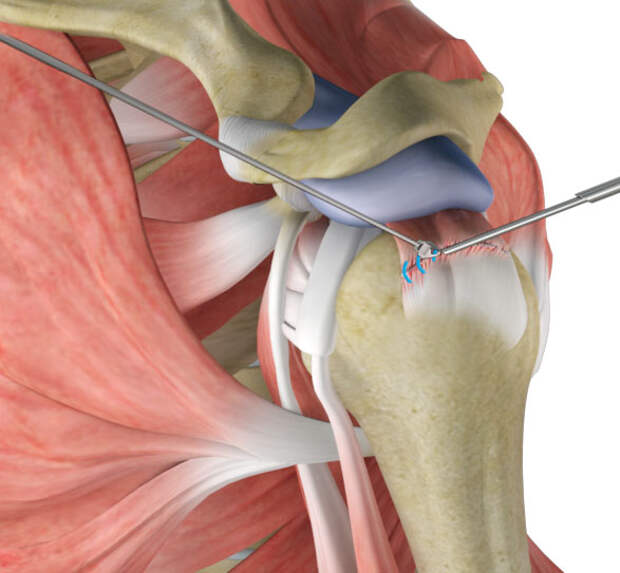

Фотографии мышц ротаторной манжеты плеча